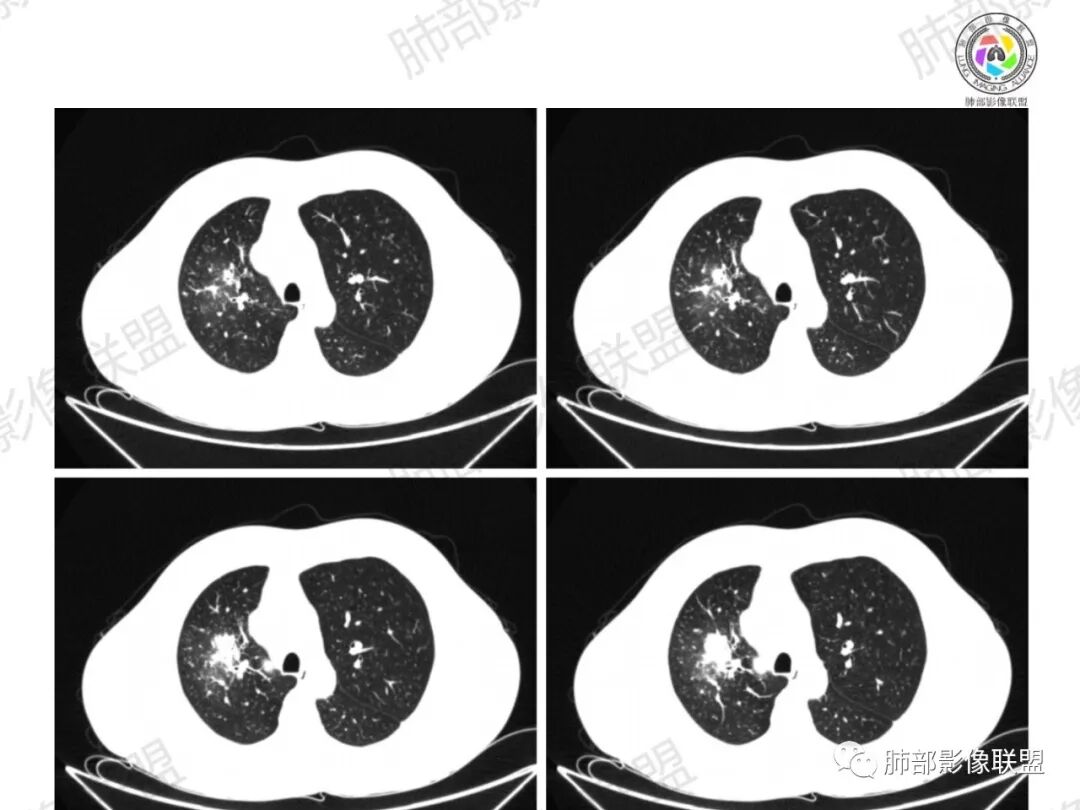

Coke with ice:病变整体收缩平直,毛刺较软,支气管壁增厚。支气管鼠尾状狭窄,于病灶以远可见显示。支气管粘液栓。相邻支气管血管推移明显,磨玻璃边缘模糊,多灶坏死边缘清晰,一部分血管自然穿行,猜个炎性病变。

这个比较大的坏死灶,边缘清晰,看似符合鳞癌坏死。仔细看看这个坏死边界,是血管阻挡引起的边界清晰。其他的病灶内低密度是柱形粘液栓。实性部分强化有轻度延迟强化。病变背景是双上肺的小叶中心结节。病变区的支气管壁是厚的。

妞妞:右肺门区病灶,边缘有GGO,模糊,远端树芽,支气管受阻,有圆钝感,病灶坏死,边缘清楚,实性成分有强化,不像鳞癌强化,首先考虑结核,鳞癌待排,建议支气管镜

良孑:右肺门肿块,有平直,u型凹陷及尖角征,远端可见散发树芽征,有支气管截断,肿块内坏死边界清,似可见围绕坏死的环状强化,综合分析首选炎性病变,TB可能,冇吸烟史,良恶性征象都有鳞癌要鉴别,

远端有些花花草草

多发树芽,病灶边缘模糊的GGO

怎么看怎么不符合恶性,远端并不是明显的阻塞性炎改变,一是主要表现为树芽和结节,二是未按责任支气管分布。

这个病例符合结核的影像表现,有以下几条:

1、坏死区内寸草不生;2、病灶环形强化;3、远端树芽和结节;4、远端不是阻塞性炎症,而是树芽和结节,右肺上叶前后段都有,后段为主,而堵塞的支气管应该是前段;这些树芽的位置不是堵塞支气管的责任区;5、支气管不是突然截断堵塞,而是逐渐狭窄;6、纵隔淋巴结是椭圆形增大,内有坏死,不是肿瘤的圆形饱满;7、支气管周围粘液样坏死,符合仙人掌结核改变;

3、阻塞性炎症:这个病例远端的散在病灶分布与责任支气管不符,所以不是阻塞性炎症,应该是树芽;

所以,这个病例应先考虑炎性病变,以结核可能性大。慢性非特异性炎症伴脓肿形成,也可以这样的影像改变,但解释不了周围的树芽和结节。